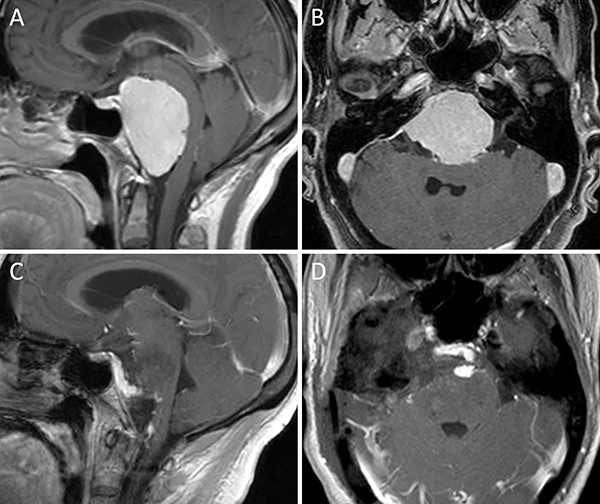

Figura 10. Meningioma del foramen magno lateral. A-B: RM preoperatoria; C-D: RM postoperatoria.